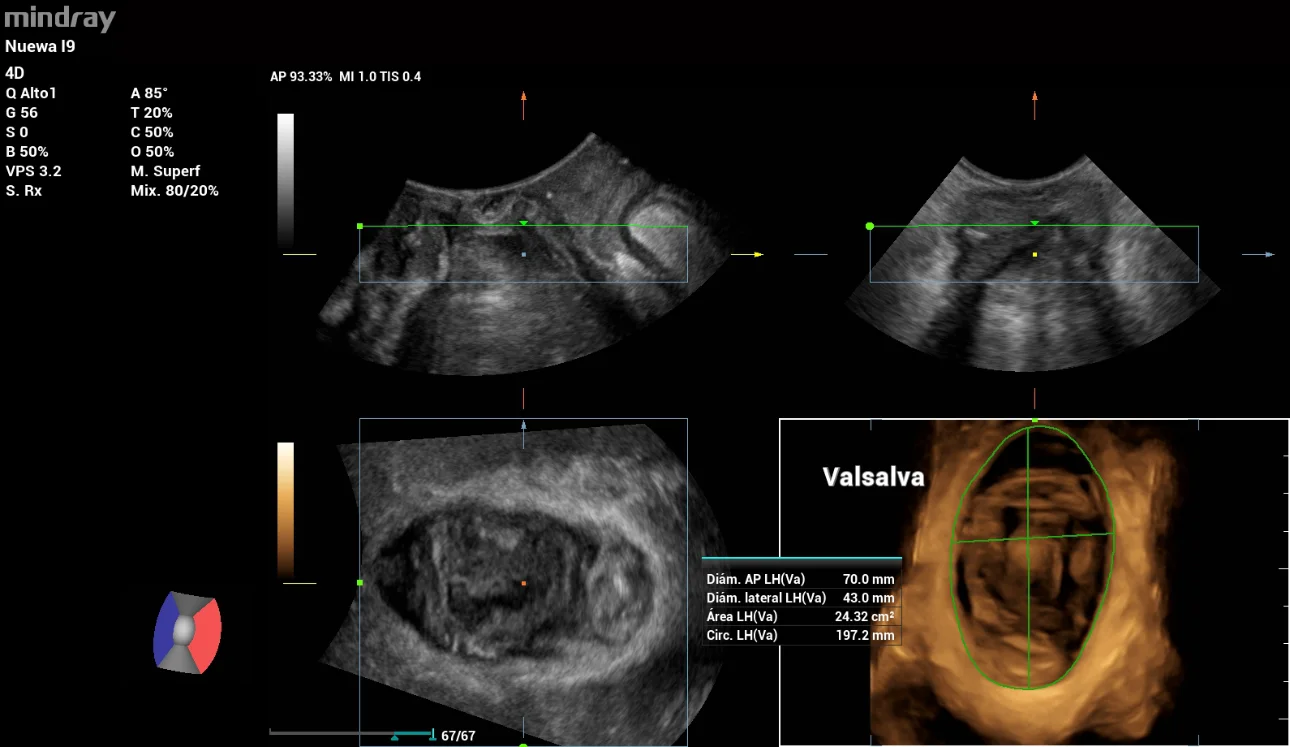

In the 3D/4D scanning, the Levator ani muscle status is intact, evaluated by the multi-slice tool iPage in contraction and the measures were: Left GAP 17mm, Right GAP 19mm (Figure 4). The Levator hiatal area in Valsalva was 24cm2 within normal values. (Figure 5)

pelvic-floor-ultrasound-stress-incontinence-fig5

Figure 5: Levator hiatal area evaluation in Valsalva with Mindray Smart Pelvic tool